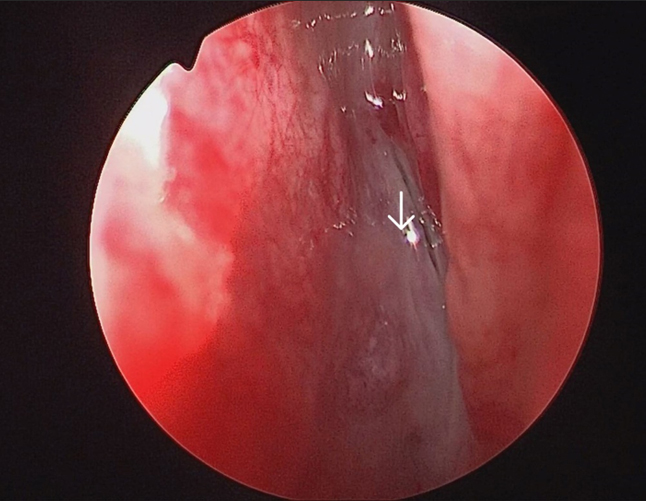

The surgery was performed under general anaesthesia by the first author. Nasal endoscopic examination after administering general anaesthesia showed watery discharge from the region of the left cribriform plate (figure3 B) and the left spheno-ethmoidal recess (figure 4). The surgery proceeded with left partial middle turbinectomy and widening of the sphenoid ostium on the left side. This was followed by left uncinectomy, middle meatal antrostomy, left anterior ethmoidectomy an removal of basal lamella and posterior ethmoidectomy. This was followed by clear delineation of the leak in the left cribriform plate and a wide sphenoidotomy (figure 5). The edematous sphenoid sinus mucosa was removed and the meningoencephalocele was seen in the left lateral recess above the vidian-rotundum line. The sphenoplalatine foramen was identified and the sphenopalatine artery cauterized. The medial aspect of the posterior wall of left maxillary sinus was removed partially. The upper part of the pterygoid process was drilled out and widened laterally exposing the antero-medial temporal lobe and the meningoencephalocele (figure 6) and the continuous csf leak leak identified.

Figure 3B. Arrow showing leak in the left cribriform plate